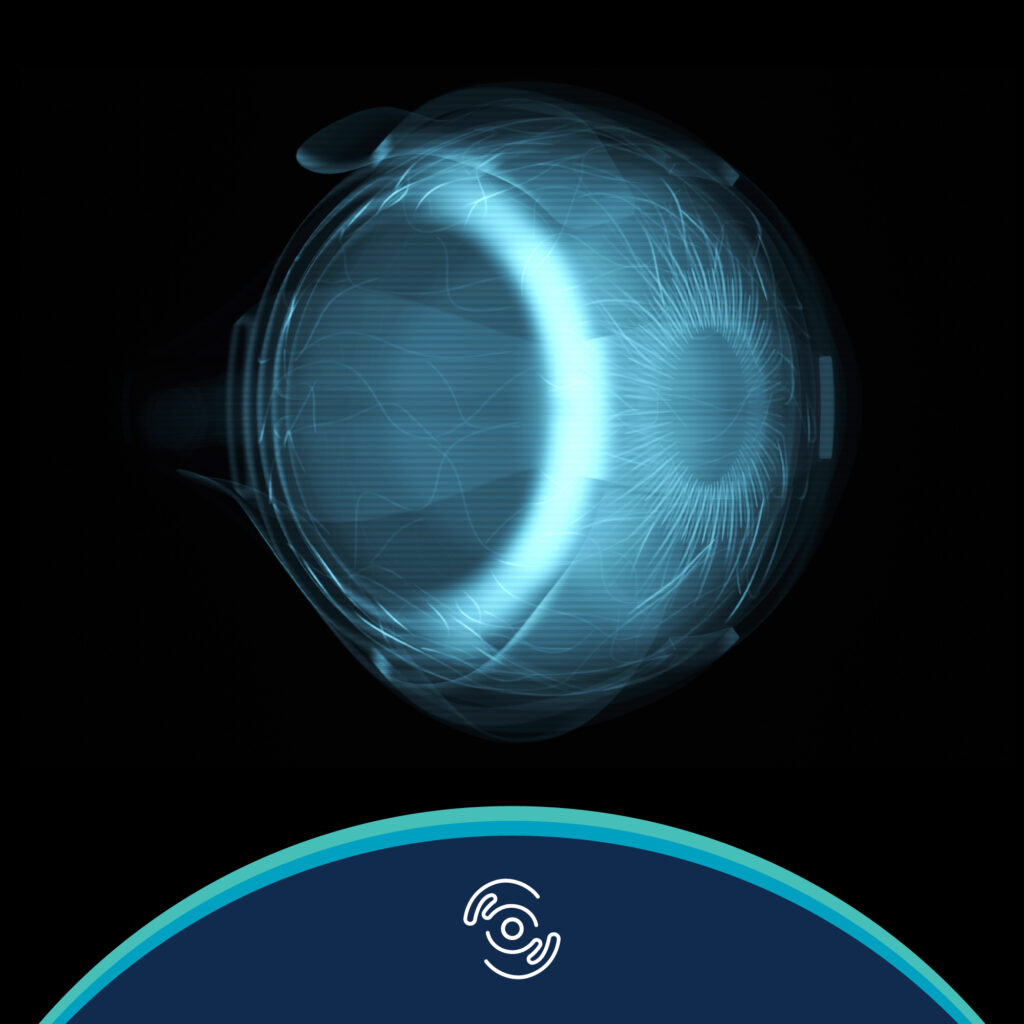

Duong, HV (2013). Corneal Embryology. In Copeland and Afshari, Principles and Practice of Cornea (Two Volume Set), 1st ed

Duong, HV (2013). Corneal Physiology. In Copeland and Afshari, Principles and Practice of Cornea (Two Volume Set), 1st ed. Jaypee Brothers Publisher. New Delhi, IN.

Duong, HV. Eye Globe Anatomy. Medscape Reference. Updated 9 November 2017.

Duong, HV. Visual System Anatomy. Medscape Reference. Updated 9 November 2017.